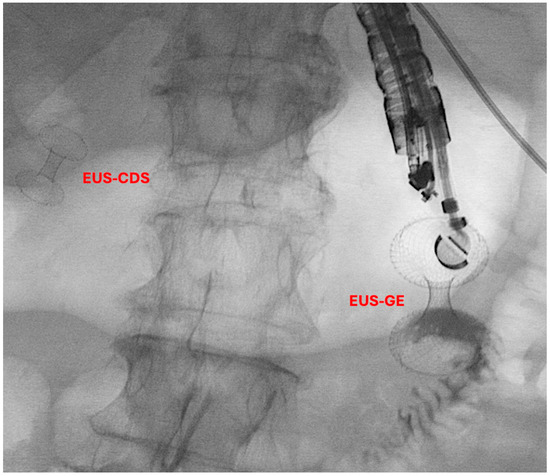

Historically, the treatment options for GOO have included surgical gastroenterostomy (S-GE) and enteral stenting (ES), which involves placing a metal stent through the stenosis [52]. While S-GE is highly effective, it is a surgical intervention associated with a notable risk of morbidity due to surgical complications and is often not feasible for patients unfit for surgery, such as those with advanced oncological disease. ES, on the other hand, is a minimally invasive procedure with a lower risk of AEs and good short-term efficacy [53]. However, it is frequently associated with stent obstruction, necessitating reintervention [54,55]. In this context, EUS-guided gastroenterostomy (EUS-GE) has emerged as a minimally invasive endoscopic alternative to S-GE for managing GOO. Like S-GE, EUS-GE involves creating a gastro-jejunal anastomosis, approximately 20 mm in size, by placing a fully covered dumbbell-shaped Lumen-Apposing Metal Stent (LAMS) under EUS guidance downstream of the obstruction (Figure 3) [13,56,57].

An international multicenter retrospective study by Bronswijk M et al. recently compared outcomes of same-session double EUS-guided bypass (EUS-GE + EUS-BD) with S-GE and hepaticojejunostomy (S-HJ) in 154 patients, 53 in the EUS group and 101 in the surgery group [81]. In the EUS-BD cohort, EUS-CDS was performed in 29 patients, EUS-HGS in 16, EUS-AS in 7, and EUS-RVS in 1. The study’s primary endpoint was clinical success (CS), defined as a GOOS ≥2, along with a post-procedural decrease in bilirubin >50% within one month or successful treatment of cholangitis. Baseline comparisons showed that patients in the EUS group had higher ASA scores and Charlson Comorbidity Index scores (9.0 [IQR, 7.0–10.0] vs. 7.0 [IQR, 5.0–9.0], p < 0.001) compared to those in the surgery group. Technical success (TS) rates were similar between the groups (96.2% vs. 100%, p = 0.117), as were CS rates (90.6% vs. 82.2%, p = 0.234). However, per-protocol analysis indicated a significantly higher CS rate in the EUS group (94.1% vs. 82.2%, p = 0.049), mainly due to a higher clinical failure rate in the S-GE group. The EUS-GE group also had a significantly shorter median time to oral intake (0 days [IQR, 0–1] vs. 6 days [IQR, 3–7], p < 0.001). For different EUS-BD approaches, no differences were observed in TS and CS rates when comparing EUS-HGS with other approaches. The surgery group, however, had a significantly higher overall adverse event (AE) rate (11.3% vs. 34.7%, p = 0.002) and severe AE rate (3.8% vs. 19.8%, p = 0.007) compared to the EUS group. Among EUS-BD procedures, EUS-AS had a significantly higher AE rate compared to EUS-HGS (0% vs. 42.9%, p = 0.020). Secondary outcomes further favored the EUS group, showing a significantly shorter hospital stay (4.0 days [IQR, 3–9] vs. 13 days [IQR, 9–22], p = 0.001) and shorter procedural time (51 min [IQR, 32–77] vs. 198 min [IQR, 139–263], p < 0.001). A sub-analysis revealed that EUS-CDS was associated with a shorter hospital stay (4 days [3–9] vs. 4 days [3–9], p = 0.026) and procedural time (50 min [IQR, 32–75] vs. 47 min [IQR, 32–73], p = 0.014) compared to EUS-HGS. No differences in biliary obstruction recurrence were observed between the EUS and surgery groups or among the various EUS-BD approaches during follow-up [81].